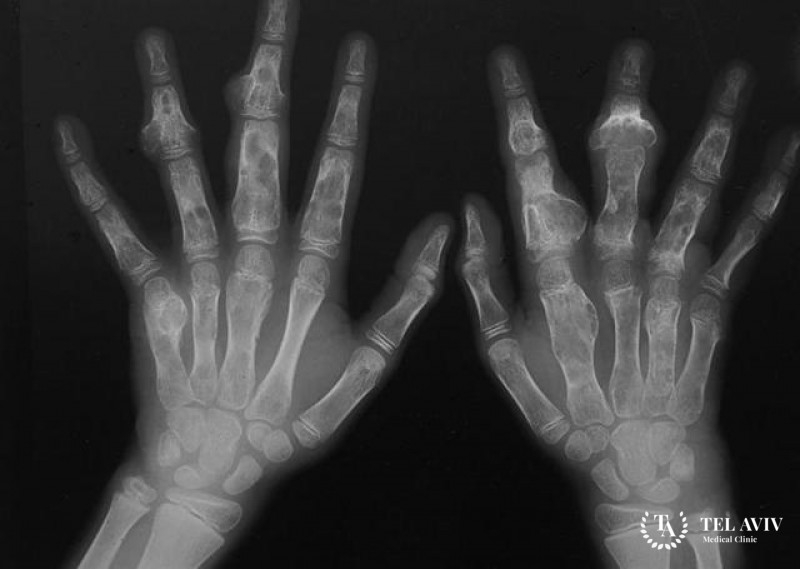

- Трубчатая кость на кисти, стопе. Признаком патологии является формирование уплотненного участка, сопровождаемое сильным болевым синдромом. Боли обусловлены компрессией нервных окончаний новообразованием;